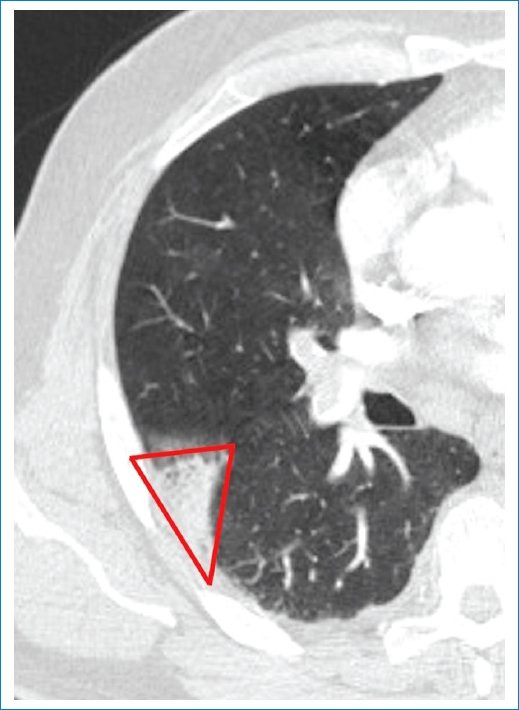

- Opacidad en cuña: presenta una especificidad del 60% y una sensibilidad del 52%5. Se trata de uno de los signos más característicos de IP, se describe como una opacidad de base pleural ancha y vértice dirigido hacia el hilio pulmonar de forma triangular, ubicada a lo largo de la superficie de la pleura visceral (costal, diafragmática, mediastínica o interlobular)3. La asociación de dicha opacidad con EP fue descrita por primera vez por Hampton en 1940 y es conocido como “joroba de Hamptom”, donde encontraron que dicha morfología en cuña era más probable en las consolidaciones observadas en pacientes con EP que en pacientes sin EP7. Como ya hemos mencionado, la ubicación periférica se debe a la afección de las ramas subsegmentarias de la arteria pulmonar, que además explicaría el dolor pleurítico y el frote pleural característicos de este cuadro clínico (Fig. 2).

Si bien la forma de cuña es la forma clásicamente descrita relacionada con IP, se ha encontrado en los últimos años que también puede adoptar morfología redondeada o de bordes irregulares, siempre manteniendo su ubicación periférica (Fig. 3)6.